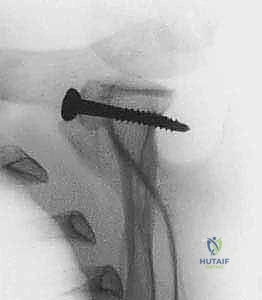

5. النقل والتثبيت (Fixation):

يتم وضع القطعة العظمية (الناتئ الغرابي) في المكان المخصص لها على حافة التجويف الحقاني بشكل مثالي. ثم تُثبت بإحكام باستخدام برغيين من التيتانيوم الطبي عالي الجودة أو مسامير ذاتية التحلل، مما يضمن ثباتاً ميكانيكياً فورياً.